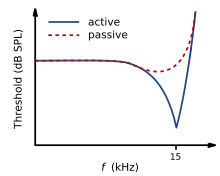

If a sound entering the ear is displaced from the characteristic frequency, then the strength of response from the basilar membrane will progressively lessen. The fine tuning of the basilar membrane is created by the input of two separate mechanisms. The first mechanism being a linear passive mechanism, which is dependent on the mechanical structure of the basilar membrane and its surrounding structures. The second mechanism is a non-linear active mechanism, which is primarily dependent on the functioning of the OHCs, and also the general physiological condition of the cochlea itself. The base and apex of the basilar membrane differ in stiffness and width, which cause the basilar membrane to respond to varying frequencies differently along its length. The base of the basilar membrane is narrow and stiff, resulting in it responding best to high frequency sounds. The apex of the basilar membrane is wider and much less stiff in comparison to the base, causing it to respond best to low frequencies.[14]

This selectivity to certain frequencies can be illustrated by neural tuning curves. These demonstrate the frequencies a fiber responds to, by showing threshold levels (dB SPL) of auditory nerve fibers as a function of different frequencies. This demonstrates that auditory nerve fibers respond best, and hence have better thresholds at the fiber's characteristic frequency and frequencies immediately surrounding it. The basilar membrane is said to be ‘sharply tuned’ due to the sharp ‘V’ shaped curve, with its ‘tip’ centered at the auditory fibers characteristic frequency. This shape shows how few frequencies a fiber responds to. If it were a broader ‘V’ shape, it would be responding to more frequencies (See Figure 4).[13]

IHC vs OHC hearing loss

A normal neural tuning curve is characterised by a broadly tuned low frequency ‘tail’, with a finely tuned middle frequency ‘tip’. However, where there is partial or complete damage to the OHCs, but with unharmed IHCs, the resulting tuning curve would show the elimination of sensitivity at the quiet sounds. I.e. where the neural tuning curve would normally be most sensitive (at the ‘tip’) (See Figure 5).[14]

Where both the OHCs and the IHCs are damaged, the resulting neural tuning curve would show the elimination of sensitivity at the ‘tip'. However, due to IHC damage, the whole tuning curve becomes raised, giving a loss of sensitivity across all frequencies (See Figure 6). It is only necessary for the first row of OHCs to be damaged for the elimination of the finely tuned ‘tip’ to occur. This supports the idea that the incidence of OHC damage and thus a loss of sensitivity to quiet sounds, occurs more than IHC loss.[14]